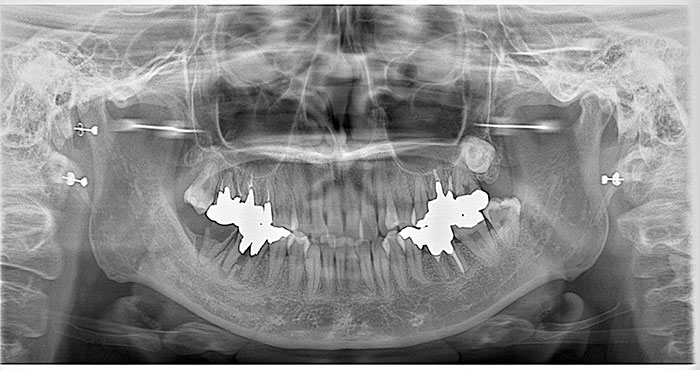

歯の移植の症例

Before

After

歯の移植をしたレントゲン写真です。

再生治療:左下水平埋伏智歯の抜歯とCGF

CGF(再生療法)

親知らずの抜歯後(傷口)をきれいにする再生療法です。

患者自身の血液から採取した成長因子を濃縮したCGFを使用し、骨や歯周組織の再生を促進する治療法です。